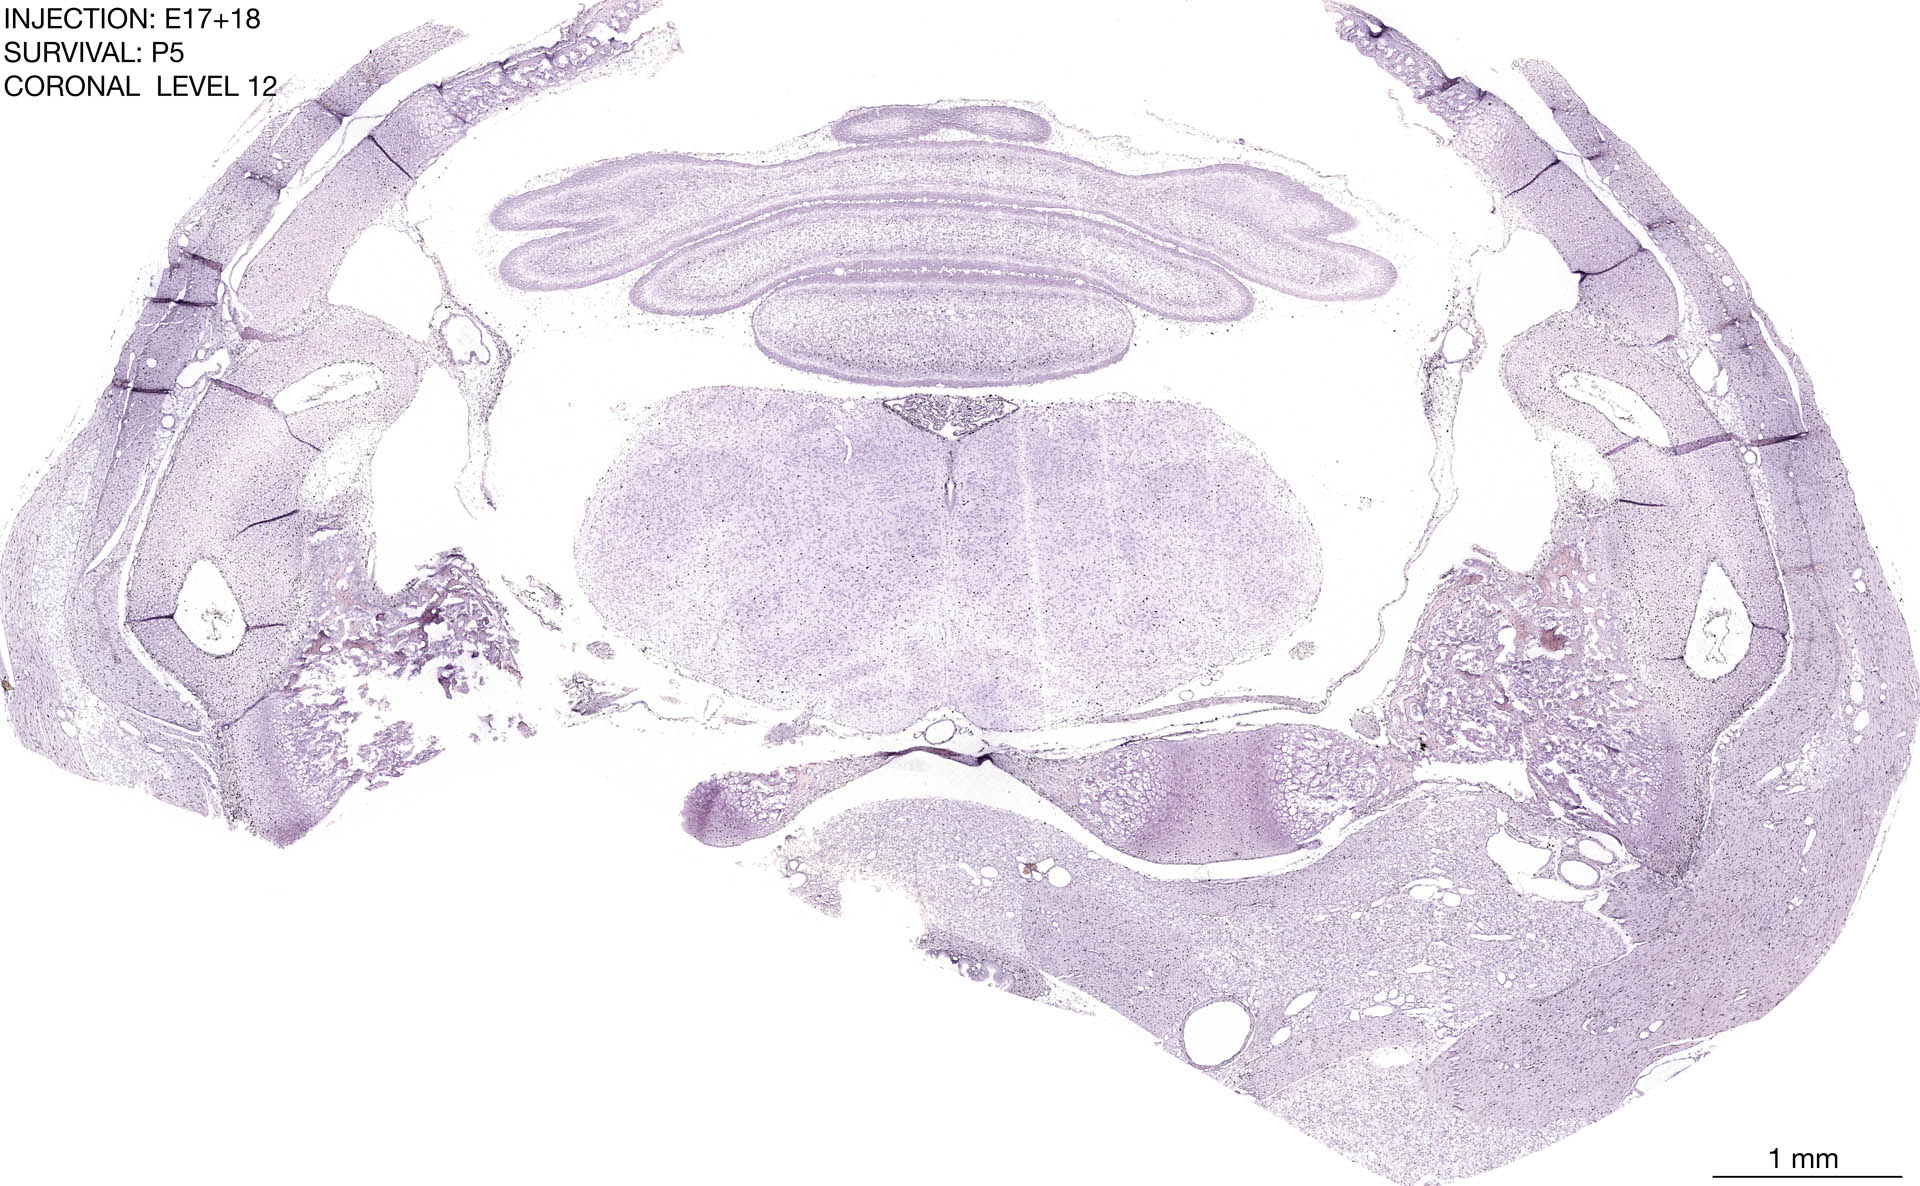

E17+18 P5 Survival The images below are from the brain of a rat that was exposed to tritiated thymidine on E17+18 and survived to P5. Download: Large | High Res Download: Large | High Res Download: Large | High Res Download: Large | High Res Download: Large | High Res Download: Large | High Res Download: Large | High Res Download: Large | High Res Download: Large | High Res Download: Large | High Res Download: Large | High Res Download: Large | High Res Download: Large | High Res Download: Large | High Res Download: Large | High Res Download: Large | High Res Download: Large | High Res Download: Large | High Res Download: Large | High Res Download: Large | High Res Download: Large | High Res Download: Large | High Res Download: Large | High Res Download: Large | High Res Download: Large | High Res Download: Large | High Res